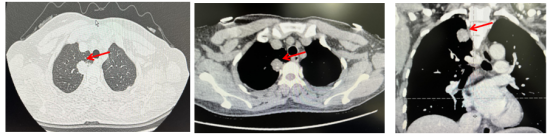

2019-03-18复查出现肺转移(术后17个月)(1)胸部增强CT:右肺上叶尖段占位:考虑恶性肿瘤,转移瘤?原发?(大小2.5*2.5cm)。(2)全腹部增强MRI示:乙状结肠癌根治术改变,吻合口区未见明显恶性征象;左侧前庭大腺囊肿增大,建议随访;盆底腹膜略增厚同前,盆腔微量积液;DWI上骨盆骨质弥漫信号增高同前。(3)全身骨显像:L4-5椎体血运丰富、代谢旺盛,多考虑良性病变;下颌骨左侧齿槽炎;颅骨骨质疏松改变。(4)CEA、CA19-9正常范围

image.png

图2 术后17个月复查的影像学结果